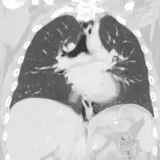

Over 2,100 interactive radiology cases, curated by radiologists for your level of training. Scroll, window, and view cases full screen — just like on PACS. Click linked findings in each writeup to jump straight to them on the image. Cases include sample reports, a focused discussion section, original illustrations, and videos.

Casos totalmente interativos com as ferramentas que você espera em um PACS — rolagem, ajuste de janela, zoom, movimentação, medidas, ROIs e modo de tela cheia.

Anotações detalhadas destacam os achados principais diretamente nos casos. Clique nos achados vinculados nas descrições dos casos para ir ao local exato no exame.

Role, movimente, ajuste janela e amplie como em uma estação PACS do trabalho